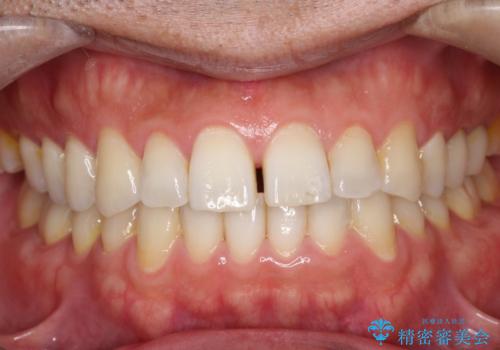

【インビザライン】前歯の隙間を閉じたい

- 前歯の隙間を主訴に来院されました。

マウスピース矯正にて、隙間を綺麗に閉じることができ満足していただきました。